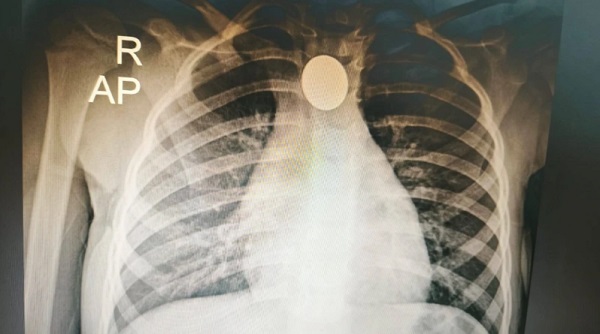

La paciente ingresó primero al Hospital de Mariano Roque Alonso con un cuadro de babeo constante. Este síntoma preocupó a su madre, quien solicitó asistencia médica de inmediato. Una radiografía confirmó que el objeto dificultaba la respiración de la niña. Por ello, los médicos ordenaron su traslado al Ineram. En dicha institución disponían de los recursos necesarios para atender la emergencia pediátrica.

El doctor Carlos Morínigo encabezó el procedimiento utilizando una técnica con una sonda y una jeringa. El especialista explicó que ingresaron al esófago para inflar un dispositivo y retirar la moneda. Morínigo destacó que este método permitió una extracción segura del cuerpo extraño. El uso de estas herramientas evitó recurrir a procesos invasivos. De esta forma, se garantizó la integridad física de la pequeña.

Una niña que tragó una moneda de 100 guaraníes fue atendida en el INERAM, donde médicos lograron extraer el objeto alojado en su esófago. El neumólogo Carlos Morínigo relató que recibió la llamada de una colega pediatra… pic.twitter.com/fIgqEUeGNC